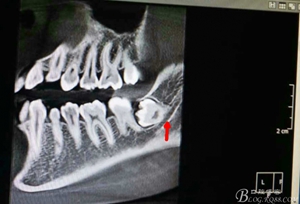

圖4.術(shù)前的CBCT縱剖面檢查:38牙根1/3緊鄰下頜管,看紅色箭頭。提示盡量不要斷根,如根尖折斷,取根導致下頜神經(jīng)損傷的風險加大